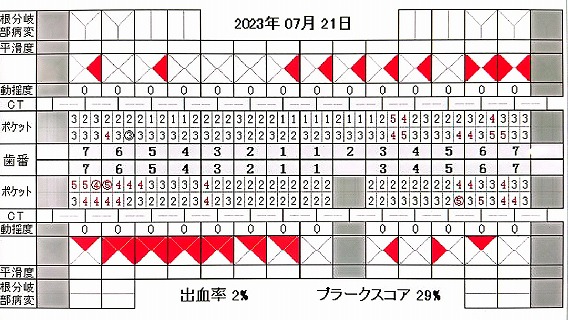

23.7.21 検査 PDF

23.10.27 検査 PDF